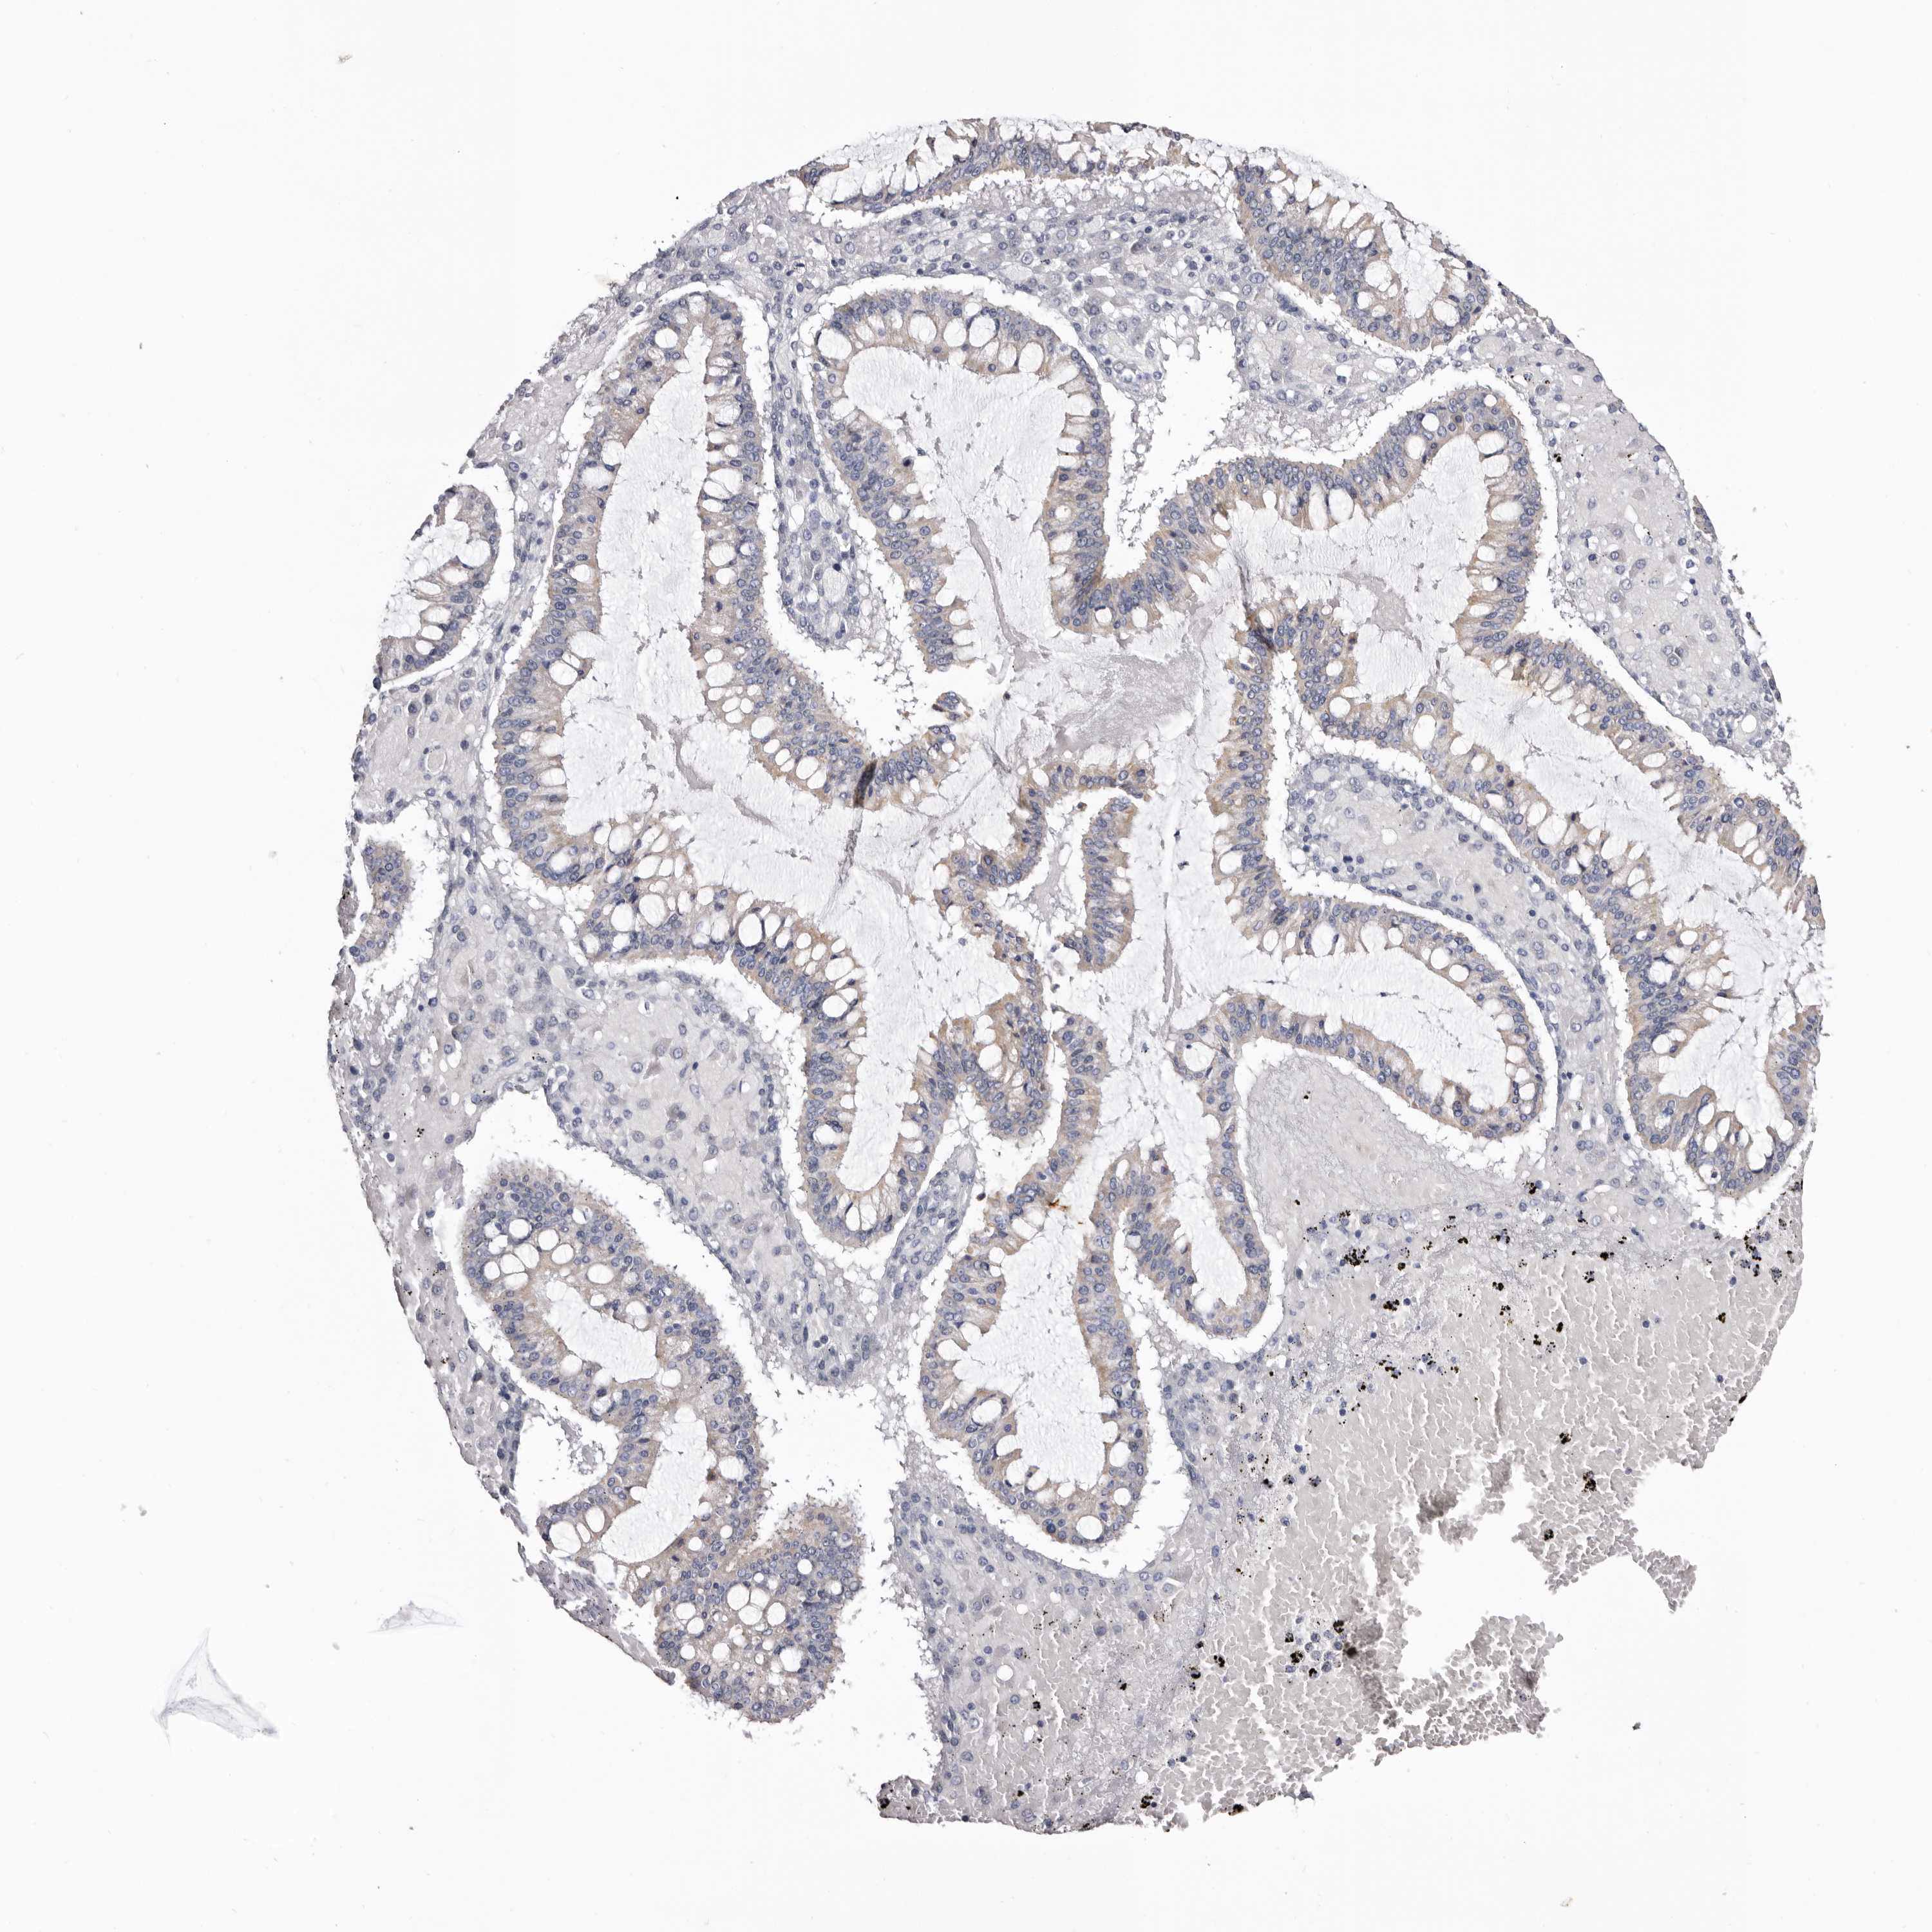

OVARIAN CANCER - Protein expressioni

A mouse-over function shows sample information and annotation data. Click on an image to view it in a full screen mode. Samples can be filtered based on level of antibody staining by selecting one or several of the following categories: high, medium, low and not detected. The assay and annotation is described here.

Note that samples used for immunohistochemistry by the Human Protein Atlas do not correspond to samples in the TCGA dataset.

Antibody stainingi

Antibody staining in the annotated cell types in the current human tissue is reported as not detected, low, medium, or high, based on conventional immunohistochemistry profiling in selected tissues. This score is based on the combination of the staining intensity and fraction of stained cells.

Each image is clickable and will lead to virtual microscopy that enables deeper exploration of all samples and also displays staining intensity scores, fraction scores and subcellular localization as well as patient and tissue information for each sample.

Antibody HPA007845

Antibody HPA026823

Antibody CAB015170

Cystadenocarcinoma, serous, NOS

Carcinoma, endometroid

Cystadenocarcinoma, mucinous, NOS

Carcinoma, NOS